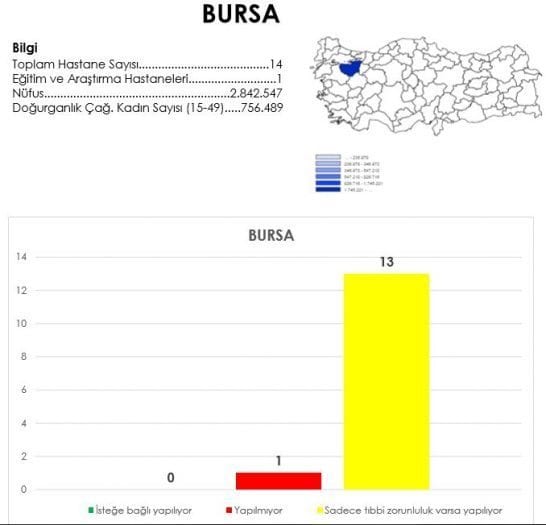

Kurtaj Yapan Hastaneler Bursa

12 Ilde Sadece 9 Kamu Hastanesi Yasaya Uygun Kurtaj Yapiyor Bianet

Kurtaj Yasal Olmasina Ragmen Yapacak Devlet Hastanesi Cok Az